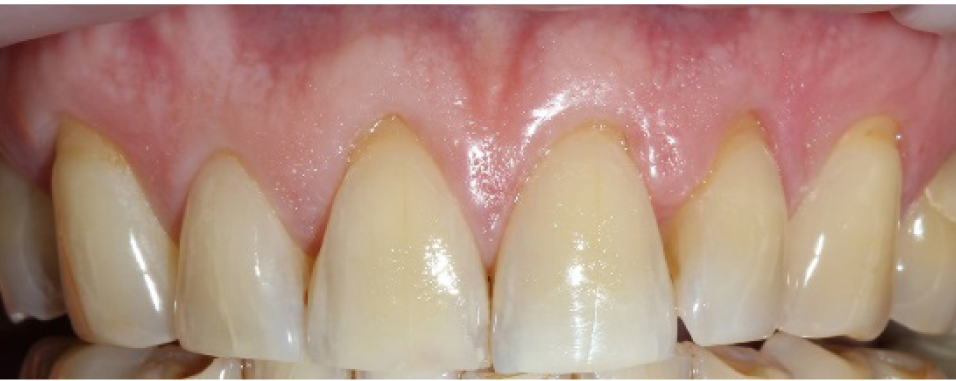

Произведен анализ 20 клинических случаев закрытия рецессий десневого края зубов на верхней и нижней челюстях по классификации Miller I и II класса, подкласса А и Б и классификации Francesco Cairo – 1-го и 2-го типа с применением туннельной техники по Zuhr (рис. 1). Операции проводились в период с 2019 по 2020 год. Средний возраст пациентов составил 31 год. Гендерное соотношение составило – 12 (60 %) женщин и 8 (40 %) мужчин, при этом на верхней челюсти произведено 13 (65 %) операций, а на нижней – 7 (35 %). Наличие гиперестезии в области зубов с рецессиями десневого края и эстетического дефекта – основные жалобы, которые предъявляли пациенты. Значение ширины зоны кератинизированной прикрепленной десны было вариабельно во всех клинических случаях и в среднем составляло 3 мм (норма – 4–9 мм). Уровень индивидуальной гигиены у всех обследованных находился на высоком уровне (PI < 20 %). Послеоперационный период наблюдения составлял от 1 года до 3 лет. Оценка эффективности устранения рецессии производилась на контрольных осмотрах через 3 и 6 месяцев, 1, 2 и 3 года путем определения следующих параметров: глубина и ширина рецессий (определение расстояния от цементно-эмалевого соединения до наиболее апикальной границы обнаженной поверхности корня), ширина зоны кератинизированной прикрепленной десны (ЗКПД), наличие или отсутствие рецидива, текстура и цвет мягких тканей в области вмешательства (оценка с помощью визуального контроля).

Рис. 1. Рецессия в области фронтальной группы зубов верхней челюсти Miller 1, Cairo Rt 1